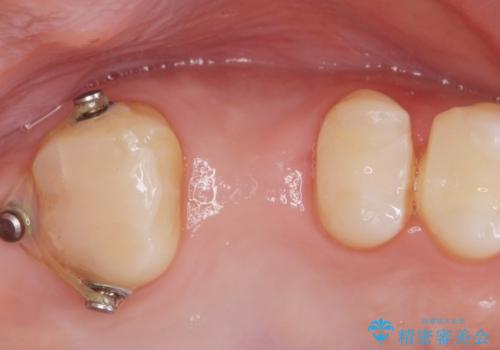

適合の良いブリッジが入りました。

歯の傾きを改善することにより食べ物が詰まりにくくなりました。

白い被せ物が入り、満足して頂けました。